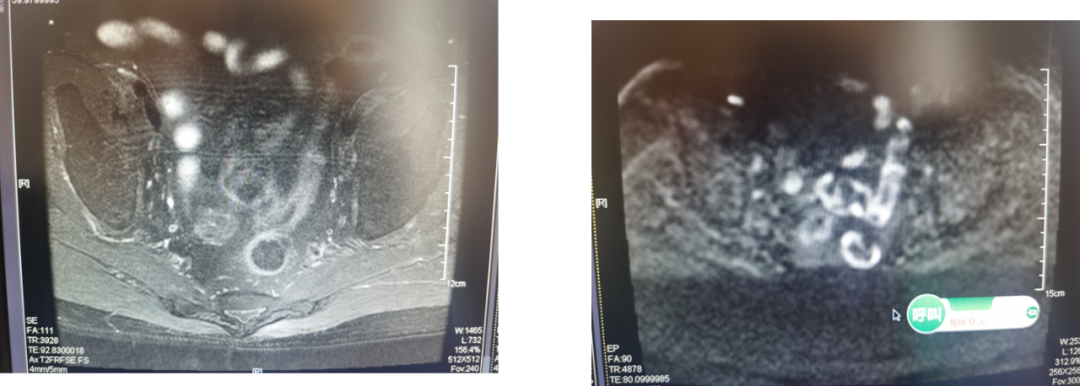

前列腺癌是典型的异质性肿瘤,由于发病隐匿,加之临床筛查工作尚未普及,所以高危进展性前列腺癌及转移性前列腺癌患者所占比例较高。其中,转移性激素敏感性前列腺癌(mHSPC)是转移性前列腺癌中预后较好的类型,但这一阶段的患者进展后将转变为转移性去势抵抗性前列腺癌(mCRPC),患者预后较差。目前,国内外多个权威指南均推荐泽珂®(醋酸阿比特龙片)用于mHSPC及mCRPC的一线治疗。本次为大家带来2例来自真实世界的病例分享,供读者交流和探讨。 病例一 病史 患者男性,78岁,主诉:前列腺特异性抗原(PSA)升高3年余。 现病史:患者3年余前体检发现PSA升高,约4.7ng/ml,后缓慢增高,未重视。2017年6月再次体检提示PSA 28.6ng/ml,外院行前列腺穿刺12针显示为前列腺腺泡腺癌,Gleason score 4+4。SPECT/CT提示全身骨转移(腰2,腰5可疑)。患者长期排尿不畅,夜尿增多(2-3次)。 直肠指诊:前列腺增大,双叶表面触及多处隆起结节质地硬,与直肠关系密切。 辅助检查 血常规:血红蛋白(Hb)126g/L,白细胞计数(WBC)4.7 x 10^9/L,血小板计数(PLT)132x10^9/L。 CT:髂血管旁淋巴结改变。 骨扫描:腰2转移腰5可疑。 图 髂血管旁淋巴结改变 图 全身骨显像 诊断结果 高危mHSPC(T3N1M1b,Gleason评分4+4=8分)。 治疗经过 2017年5月患者于外院应用5月内分泌治疗后,就诊于我院。 2017年11月患者内分泌治疗6月PSA下降至5.7ng/ml,加用原研阿比特龙1000mg联合泼尼松5mg Qd,PSA改善明显,至2020年4月,PSA下降至1.714ng/ml。 2020年7月PSA升至2.765ng/ml,遂将泼尼松换为地塞米松。 2021年4月,PSA为1.667ng/ml,月底更换国产阿比特龙。 2021年7月,PSA升至2.65ng/ml。 2021年8月,PSA为2.635ng/ml,换回原研阿比特龙。 病例分析: 本例患者为高危mHSPC患者,经内分泌治疗后,加用原研阿比特龙,PSA改善明显。国内外权威指南均推荐:醋酸阿比特龙是mHSPC患者的一线治疗方案2-4。LATITUDE研究对比了原研阿比特龙联合泼尼松(AAP)+雄激素剥夺疗法(ADT) vs 单用ADT治疗高危mHSPC患者的结果,数据显示,ADT+AAP显著延长高危mHSPC患者中位rPFS至33个月,对不同亚组的分析显示,ADT+AAP对于不同亚组高危mHSPC患者,均有一致的无进展生存期(PFS)获益,亚洲患者肿瘤转移进展风险降低近七成。原研阿比特龙组至PSA进展时间为33.2个月,对照组7.4个月,降低PSA进展风险70%。总生存期(OS)数据显示,安慰剂组中位OS为36.5个月。原研阿比特龙组为53.3个月,P值具有显著的统计学差异5。 图 LATITUDE研究结果 该患者使用原研阿比特龙32个月后,PSA显著改善,换用国产阿比特龙,PSA水平升高,这提示我们仿制药和原研药之间存在差异。原研阿比特龙是国际国内指南一线推荐治疗晚期前列腺癌的新型内分泌药物,相比仿制品,具有卓越的疗效及安全性证据。真实世界中,相比原研阿比特龙,仿制阿比特龙发生更多严重不良事件6-7。 病例提供者:马宏 教授 马宏 教授 北京医院泌尿外科 副主任医师 北京肿瘤防治研究会泌尿肿瘤委员会 副主委 北京抗癌协会泌尿肿瘤青年委员 北京中西医结合男科分会青年委员 中国研究型医院学会泌尿及男科冲击波学组委员 《中国性杂志》编委 北京大学医学部优秀教师 台大医院,柏林夏洛蒂医院访问学者 点评(万奔教授) 国产仿制药对于临床医生,多了可供选择的空间;对于患者,降低了部分支付压力。通常,仿制药的生物利用度在原研药生物利用度的80%~125%之内都认为两者具有生物等效性,但生物等效性在判定原则上会导致仿制药与原研药的生物利用度存在差异,而且会导致仿制药之间的生物利用度差异更大。在该病例中,患者换用国产阿比特龙后,PSA水平升高,提示生物等效性≠临床等效性8。对于部分高龄前列腺癌患者,基础合并疾病较多,生活质量普遍较差,如果非医疗原因换药,导致疾病波动及发生并发症的风险显著提高。因此,临床上应重点关注以上类型患者,谨慎权衡仿制药或原研药的选择9-12。期待未来中国制药产业技术的不断革新,国产仿制药品从品种到品质可以比肩原研药,保障更多患者获益。另外,此病例提示,阿比特龙联合治疗时,糖皮质激素的替换可带来患者的持续PSA减低。 点评专家:万奔 教授 万奔 教授 北京医院泌尿外科 主任医师 中国医师协会泌尿外科医师分会肿瘤专业委员会 委员 中国研究型医院学会泌尿外科学专业委员会 委员 北京抗癌协会泌尿男生殖系肿瘤专业委员会 副主任委员 北京医师协会泌尿外科专家委员会 委员 海峡两岸医药卫生交流协会泌尿外科学专业委员会 委员 中日医学科技交流协会 理事 病例二 病史 患者男性,69岁。主诉:体检发现PSA升高1周。 既往史:冠心病8年,3年前于外院行心脏冠脉支架置入术,长期口服阿司匹林和波利维抗血小板治疗。 辅助检查 实验室检查:总前列腺特异性抗原(T-PSA)149.5ng/ml。 骨扫描:右侧第3-5前肋、左侧第3/6前肋、第7后肋、第9后肋近肋椎关节处、第10胸椎、第2/5腰椎放射性摄取增高影(10处)。 前列腺MR增强:前列腺癌可能大,肿瘤突破包膜,累及精囊腺。双侧髂血管旁多发肿大淋巴结,转移可能。腰2、5椎体骨质破坏,转移可能大。 图 全身骨显像 穿刺病理:前列腺癌,12/13(+),Gleason 评分 4+5=9分,部分可见肿瘤浸润神经。 诊断结果 第一次诊断(2014年6月):高危mHSPC(T3bN1M1)。 第二次诊断(2015年2月):mCRPC。 治疗经过 2014年6月接受比卡鲁胺50mg Qd x 2w+戈舍瑞林10.8mg治疗。 2014年7月入组LATITUDE研究,PSA最低降至4.02 ng/ml。 2015年2月复查PSA升高至14.73 ng/ml,试验出组,揭盲,证实为安慰剂组;随后患者接受戈舍瑞林10.8mg+比卡鲁胺50mgQd,6个月后,PSA最低达到4.21 ng/ml。 2015年12月PSA升至9.12 ng/ml,停用比卡鲁胺,PSA水平于2016年2月回落至6.5ng/ml,8周后PSA再度上升至11.97ng/ml。 2016年6月患者接受阿比特龙1000mg Qd+泼尼松5mg Bid,PSA逐渐降低,最低至0.75ng/ml。 2017年11月将泼尼松5mg Bid换为地塞米松0.75mg Qd,PSA为2.36ng/ml。 2019年12月PSA水平缓慢上升到18.49 ng/ml,开始多西他赛+地塞米松方案化疗患者完成DP方案9周期化疗,PSA降至1.72ng/ml。 2020年7月患者因下腹隐痛行盆腔磁共振及PSMA-PET/CT检查示新发精囊转移灶,行放疗后,发现精囊癌灶变小,盆腔疼痛症状消失。 2020年11月PSA升高至3.4ng/ml,伴随新发后肋部疼痛,需口服镇痛药物缓解。复查PSMA和SSTR-PET/CT发现新发后肋部转移灶及多发肝脏病灶 ;行CT引导下肝脏病灶穿刺活检;病理:肝组织内见癌细胞浸润。 2020年11月23日多西他赛120mg+卡铂450mg化疗,化疗1周后出现中性粒细胞减低、血小板减低 CTCAE IV级,对症支持治疗1月后好转。 2021年1月开始应用恩杂卢胺治疗。 …… 图 前列腺癌患者不同治疗方案期间血清PSA水平变化情况 病例分析: 本例患者就诊时即发现全身多发骨转移,且Gleason评分4+5=9分,符合高危及高肿瘤负荷mHSPC诊断,2014年7月患者入组LATITUDE研究。LATITUDE研究为一项在新确诊为高危转移性未经激素治疗的前列腺癌患者中进行的多中心、3期、随机、双盲、安慰剂对照试验。最终分析显示,一线接受ADT+AAP的患者中位OS达4.5年,比一线接受ADT的患者延长16.8个月。因此,该患者无论接受单纯ADT,还是联合雄激素阻断治疗(CAB)都是不足够的,应首选推荐ADT联合阿比特龙的治疗方案。 图 LATITUDE研究结果 患者在mCRPC阶段应用阿比特龙联合泼尼松,经过数年的治疗,PSA控制良好,中间泼尼松换用地塞米松,继续维持阿比特龙使用,直至出现症状及影像进展。患者历经新型内分泌治疗等多种疗法,实现了长达7年的长期生存1。 病例提供者:米悦 教授 米悦 教授 北京大学第一医院 泌尿外科 主治医师 博士 北京大学泌尿外科研究所 擅长泌尿系肿瘤的微创治疗,前列腺增生、泌尿系结石的腔内治疗及晚期肿瘤的综合治疗。一直从事泌尿外科临床医疗、教学和科研工作。 2018年参加第32届“中国泌尿外科将才工程培训班”赴美国USC访问交流。累计发表国内核心期刊论文及SCI 论文6篇,参与撰写泌尿外科专著3部,翻译4部泌尿外科专著。 点评(张骞教授) 本例患者第一次被确诊为mHSPC,ADT治疗7个月后疾病快速进展为mCRPC。大部分高危/高瘤负荷的mHSPC患者在治疗初期ADT产生应答,但在ADT治疗9~15个月后发展为mCRPC。因此,对于高危mHSPC患者,临床应更早使用新型内分泌治疗。无论以PSA下降超过30%或50%作为界值,达到早期PSA应答(EPR)的患者预后均显著优于未达到EPR的患者。当患者进入mCRPC阶段后,应用ADT+AAP方案治疗1个月,患者PSA水平下降幅度达到73.4%,实现了EPR并且PSA较基线下降>50%。此后该方案在近3年内持续保持肿瘤相对控制和疾病稳定状态。该患者历经新型内分泌治疗、化疗、放疗、联合化疗和新型内分泌序贯治疗,取得了较好治疗效果,实现了长期生存。 点评专家:张骞 教授 张骞 教授 北京大学泌尿外科研究所 副所长 北京大学第一医院泌尿外科 副主任 北京大学滨海医院 院长 北京大学医学部医院管理处 处长 郭应禄泌尿外科发展基金会 副理事长 中国医师协会泌尿外科分会青年委员会 副主任委员 中华医学会泌尿外科学分会微创学组 委员 国家卫计委泌尿外科内镜诊疗技术专家组 委员 中国医促会腔镜内镜分会 常委 编者手札 在转移性前列腺癌患者的治疗过程中,通过监测PSA水平和影像学检查变化,能够及时了解患者对雄激素的敏感程度和疾病的进展情况,为治疗方案的调整和预后判断提供依据。原研阿比特龙是国际国内指南一线推荐治疗晚期前列腺癌的新型内分泌药物,首选原研阿比特龙能够为患者带来明显的PSA下降和持续的疾病控制。 备注:文中醋酸阿比特龙片简称阿比特龙 参考文献: 1.米悦,等.中华泌尿外科杂志.2021;42:19-23. 2.Advanced Prostate Cancer: AUA/ASTRO/SUO Guideline.2020. 3.European Association of Urology. Guidelines on Prostate Cancer. 2021. 4.NCCN Clinical Practice Guidelines in Oncology(NCCN Guidelines®) .2021.v2.. 5.CSCO,2021 前列腺癌诊疗指南 6.https://www.fda.gov/drugs/surveillance/fda-adverse-event-reporting-system-faers 7.Ryan CJ, et al. Lancet Oncol. 2015; 16(2):152-160. 8.黄浪,等.北方药学.2011;08(8):83-84. 9.resented by Prof. Gao Xin at 2018 CACA GU annual conference, Shanghai, Dec. 8, 2018. 10.马宝杰,等.中华泌尿外科杂志.2014;000(007):554-556. 11.Cheng Y, et al. Pharmacoepidemiol Drug Saf. 2019;28(11):1501–1509. 12.Holm M, et al. BMC Palliat Care. 2018 Dec 3;17(1):126.